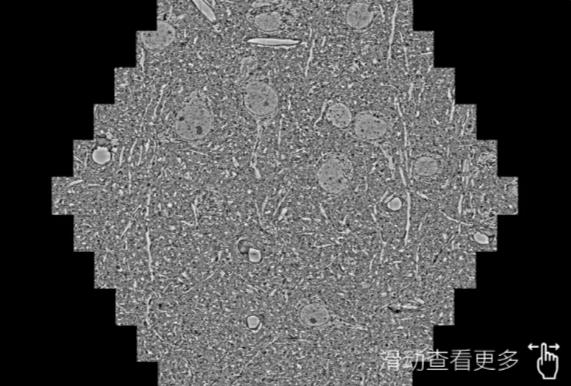

鼠脑切片。左图使用黔西南蔡司黔西南扫描电镜MultiSEM706对165μmx143pm面积区域成像,耗时仅需1.5秒。右图为鼠脑切片中30μm区域放大效果。样品由芝加哥大学B.Kasthuri提供。